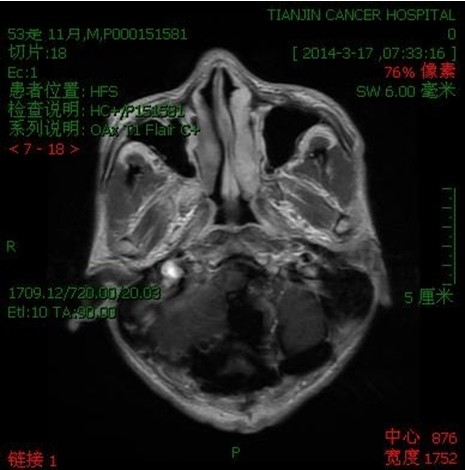

病例二:王**,男性,53岁。因做小脑肿瘤术后9年,头痛头晕,伴颈部疼痛、走路不稳半年入院。入院诊断:延颈交界血管网织细胞瘤。术式:后正中入路延颈交界区血管网织细胞瘤切除术。术后病理:血管网织细胞瘤。术后头痛头晕,颈部疼痛消失,走路平稳。

术前

术后